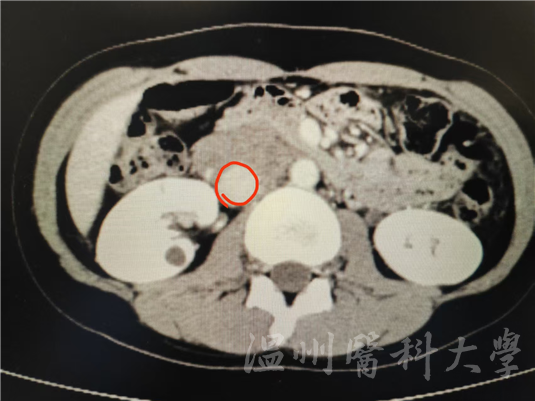

包裹住张女士下腔静脉肿瘤

“这个肿物拆除难度极大!”疝与腹壁外科科主任杨越涛介绍,下腔静脉是人体重要的大血管,肿物与血管、周围组织紧密粘连,稍有不慎就可能损伤血管,引发大出血,手术难度极高,而张女士的肿物几乎是完全包裹住了下腔静脉。